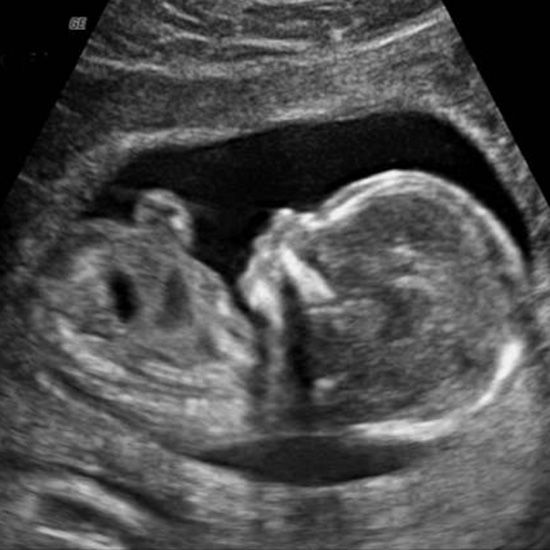

Morfologiile fetale

Spre deosebire de ecografiile de rutină, morfologiile fetale sunt teste de screening mai ample, care oferă detalii cu privire la dezvoltarea bebelușului și, eventual, potențiale diagnostice. Se face câte o morfologie fetală pe trimestru, în cadrul căreia medicul analizează capul și creierul bebelușului, coloana vertebrală, peretele abdominal, organele, stomacul, brațele, picioarele, cordonul ombilical, placenta și lichidul amniotic.

„De asemenea, în cursul ecografiei, se evaluează dimensiunea, maturitatea și poziția placentei față de colul uterin. În cazul unei operații de cezariană anterioare se evaluează integralitatea cicatricei uterului și se observă dacă placentă care acoperă peretele frontal al uterului nu s-a unit cu cicatricea. Această este o informație esențială pentru monitorizarea sarcinii de către medicul ginecolog la pregătirea planului de naștere.”, adaugă medicul Chioveanu.